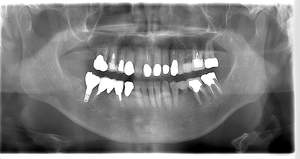

インプラント治療の症例2

レントゲン写真

- Befor

- After

| 年齢 | 50代・男性 |

|---|---|

| 主訴 | 左上7番 左下5番7番 |

| 治療内容 | ・インプラント埋入 ※1:GBR(骨造成)・・・骨再生誘導法。骨の高さや厚みを人工骨や人工膜などを使用し再生する方法 |

| 治療費 | 合計:1,809,500円(税込) ■内訳 ・左上7番 ・左下5番7番 |

| 治療期間 | 左上7番約1年 左下5番7番約10ヵ月 |

| 治療方針 | 左上7番は昔他院で被せものをしており、被せものの中が歯ぐきの中まで虫歯になっていたため抜歯せざるを得ない状態だった。抜歯と同時に骨造成を行い、骨が出来るまで4ヵ月待ってからインプラントを埋入した。 ※2ポンティック・・・歯のない部分を補うダミーの歯。 |

| 担当者所見 | 元々金属の被せものが多く入っていたため、2次カリエス※3が多かった。今回は金属ではなく、ジルコニアを使用し、2次カリエスにならないよう、患者様にはブラッシング指導とメンテナンスの重要性をお伝えした。 ※3二次カリエス・・・詰め物や被せものを入れた歯が虫歯になること。 |